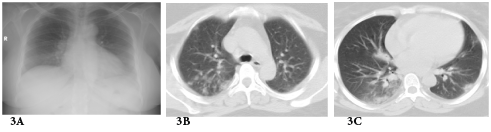

Graft failure occurred in 2 patients; one of them had already high serum creatinine at diagnosis (3mg/dl) and started dialysis 1year after H1N1 infection while the other has normal serum creatinine at diagnosis (1mg/dl) and was presented 1year later due to unexplained graft dysfunction. Some authors believe that influenza virus is capable of activating immunologic mechanisms leading to allograft rejection.9 The activation of such immunological mechanisms is related to production of interleukin -1, TNF, IL-6 and IL-8 during viral replication.10 The time interval for incidence of H1N1 infection started from the second half of December till the second half of January. Other series documented the incidence between the second half of July up to September in Asia (Singapore)8 while the largest number of confirmed cases of 2009 influenza A (H1N1) infection in North America occurred between March and July 2009.11 H1N1 infections has many complications in RTR including respiratory, cardiac and CNS sequences. However, the most common prescribed complication among RTR in the literature is respiratory complications. In one of early reports described 2 RTR that developed hypoxic respiratory failure and necessitated noninvasive ventilation12 while Singapore report described 2 mortalities among 10 cases of pneumonia.8 Other complications included H1N1 related myocarditis13 or encephalitis.14 In our series, only respiratory complications were encountered as previously mentioned. Our cases have excellent prognosis, most probably due to early initiation of oseltamivir therapy, doubling the dose and extension of the duration of treatment. Also temporary reduction of anti-proliferative drug may help RTR to recover early. Three cases of pneumonia showed inconclusive CXR while CT chest revealed bilateral infiltrates and this signifies the importance of CT chest in diagnosis of pneumonia in immune-compromised patients see Figure 3. Serial CXR was carried out to follow up lung recovery in cases of H1N1 pneumonia and it was correlated with the clinical response (Figure 4). The suspected number of RTR in December -2009 was 36 RTR which is double the number of suspected number in December-2010,this may be due to two facts; the first is vaccination with seasonal and novel H1N1 vaccine while the second is familiarity of criteria of diagnosis which reduced the number of suspected RTR.

Figure 3 Radiological diagnosis of H1N1 pneumonia in a 40-year-old female renal transplant recipient who suffered from fever and dyspnea of 2 days duration.